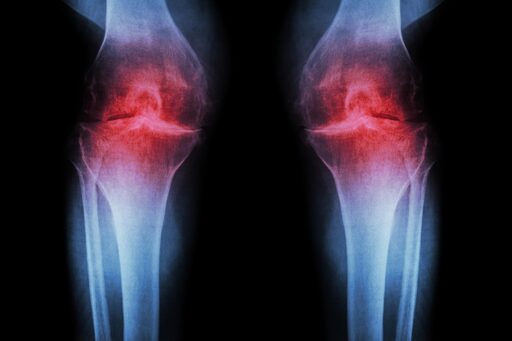

Researchers at Stanford Medicine report that blocking a protein linked to aging can restore cartilage that naturally wears away in the knees of older mice.